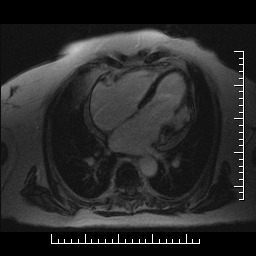

ANEURYSMA A PSEUDOANEURYSMA LEVÉ KOMORY SRDEČNÍ – DIFERENCIÁLNÍ DIAGNOSTIKA POMOCÍ MAGNETICKÉ REZONANCE DOPLNĚNÁ KAZUISTIKAMI

Diferenciální diagnostika aneurysmatu a pseudoaneurysmatu levé komory srdeční je stále obtížná. Aneurysma je definováno jako vyklenutí stěny komory deformující v diastole její typický tvar. Vzniká v důsledku přeměny stěny komory v jizvu a následným působením nitrokomorového tlaku. Oproti tomu pseudoaneurysma vzniká jako postupná ruptura stěny levé komory krytá přilehlým perikardem. Klinický důsledek rozlišení obou stavů je obrovský, protože pseudoaneurysma je vzhledem ke svému riziku ruptury indikací k operačnímu řešení. V primární diagnostice je dnes stále ještě rychlou a dostupnou metodou echokardiografie, avšak vzhledem ke špatné přehlednosti zejména v oblasti spodní a zadní stěny levé komory, kde je pseudoaneurysma nejčastěji lokalizováno, je dnes často využívanou zobrazovací metodou magnetická rezonance. Jde o neinvazivní zobrazovací vyšetření, bez radiační zátěže, s vysokou rozlišovací schopností. V rámci jednoho sezení lze provést vyšetření kinetické, morfologické i postkontrastní (first-pass, late-enhancement). Po podání kontrastní látky se u pseudoaneurysmatu objevuje pozdní sycení perikardu, jehož intenzita signálu je stejná nebo větší než u myokardiální jizvy. Na rozdíl od toho u aneurysmatu je pozdní sycení perikardu vzácné.

Uvádíme 5 krátkých kazuistik (aneurysma spodní stěny, aneurysma hrotu, aneurysma interventrikulárního septa, pseudoaneurysma zadní stěny, stav po resekci pseudoaneurysmatu) včetně obrazové dokumentace, kde vyšetření magnetickou rezonancí přispělo ke stanovení klinické diagnózy a k určení dalšího postupu.